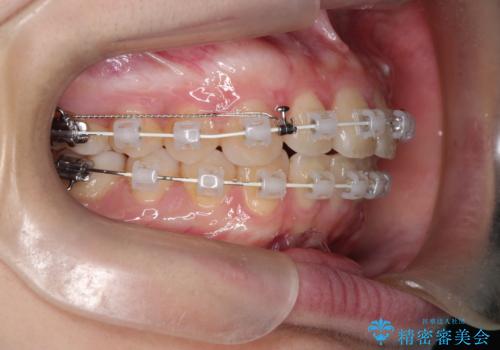

途中、矯正用のアンカースクリューを使うことで、最終的にきれいに前歯の真ん中を合わせることができました。

矯正用アンカースクリューを使用することで、歯の移動量をコントロールできるため、治療の仕上がりをよくすることができます。